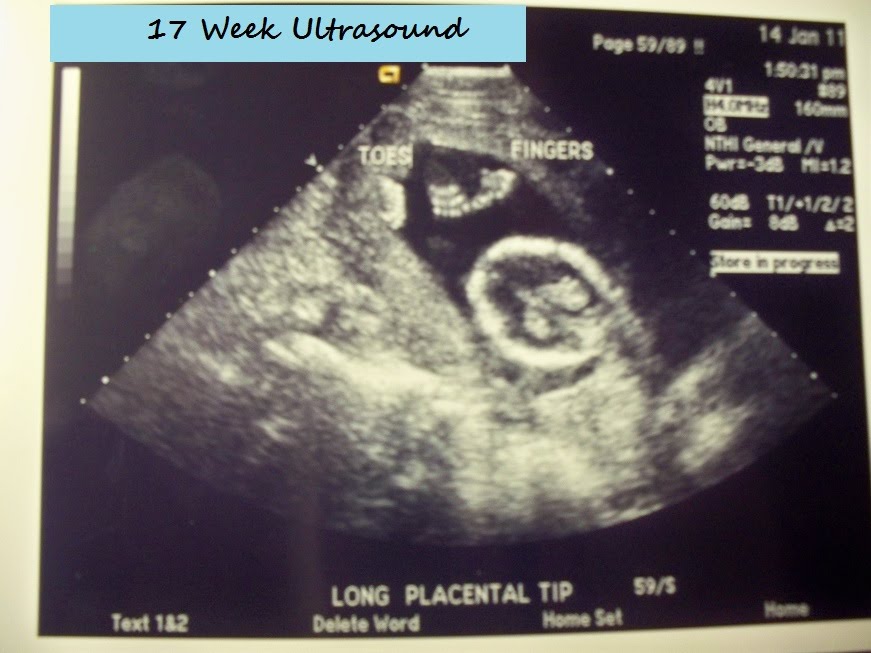

{17 weeks pregnant}

{BOY!!!!}

Just wanted to give you guys a mini-update on baby {His name is going to be Wyatt!}